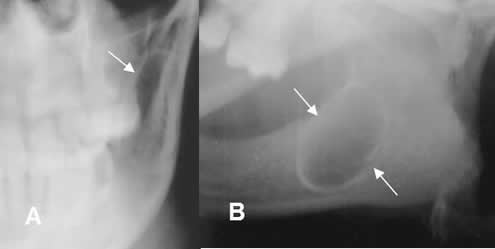

Fig 67. Queratoquiste odontogénico.

A: Rx AP y B: Rx oblicua. Imagen ovalada, de bordes bien definidos y escleróticos,

en el ramo de la mandíbula, por queratoquiste odontogénico.